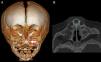

La exploración física reveló un vestíbulo nasal estrecho e imposibilidad de pasar una sonda K30 (diámetro 2,8mm) hacia la fosa nasal. La TC evidenció estenosis ósea de la AP a expensas de ambas ramas ascendentes del hueso maxilar, con calibre de coanas normal, y en 3 pacientes, un megaincisivo superior central (fig. 1). En todos los casos se midió el diámetro transverso máximo de la AP entre la cara medial del hueso maxilar a nivel del meato inferior, en el corte axial, siendo la media de 4,82mm (fig. 2). A 2 pacientes se les realizó una tomografía helicoidal con reconstrucción tridimensional (3D), que mostró la disminución de la luz nasal.

El diagnóstico de certeza se realiza mediante una TC del macizo craneofacial, donde se observa la disminución del diámetro del área nasal a nivel de la AP, mientras que las coanas son de calibre normal. El diámetro transverso de cada orificio piriforme menor de 3mm o un diámetro transverso total menor de 11mm, en recién nacidos a término, confirma el diagnóstico1,5,8. Otros hallazgos radiológicos que se asocian frecuentemente son alteraciones en la dentición (megaincisivo central único) y paladar duro triangular con una cresta en la línea media5,6.

La tomografía 3D permite una visión completa de la AP en su plano frontal, lo que posibilita medir su amplitud y una definición exacta del área ósea que debe ser resecada2,3.